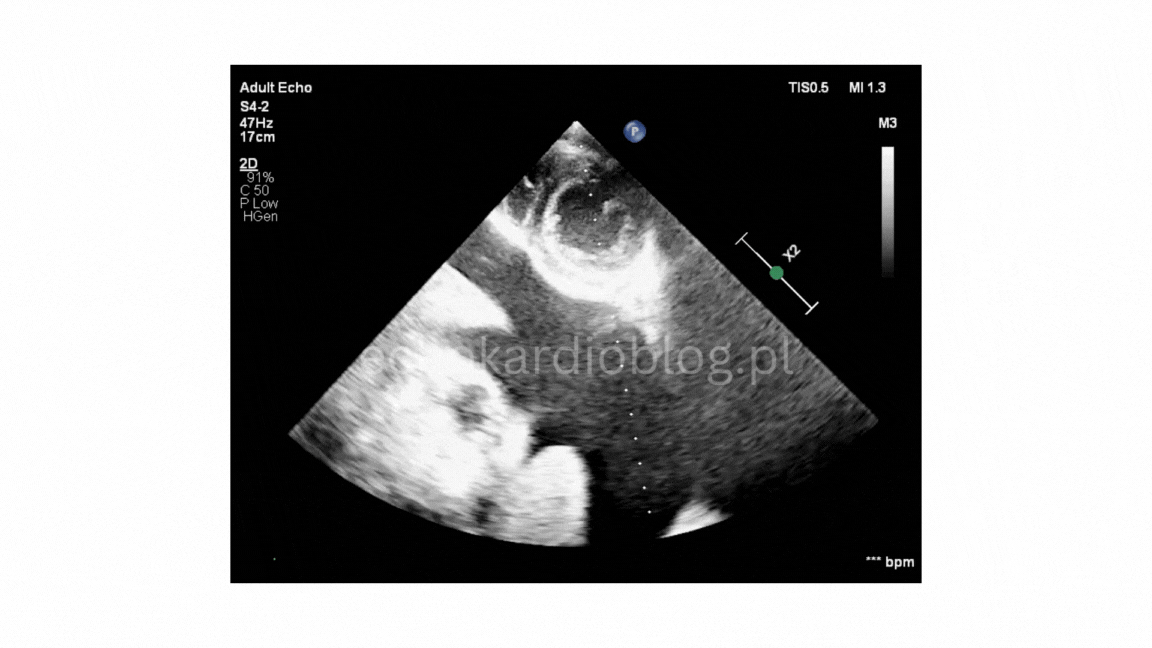

Prezentuję dwa przypadki pseudodyskinezy u pacjentów z marskością wątroby z wodobrzuszem:

przypadek 1 – silnie wyrażona jest pseudodyskineza i

We present two cases of pseudodyskinesia in patents with liver cirrhosis and ascites:

Case 1- marked pseudodyskinesia, and